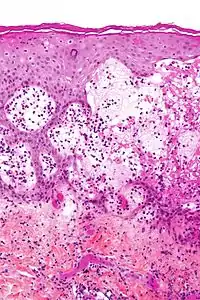

| Micrograph of gestational pemphigoid showing the characteristic subepidermal blisters and abundant eosinophils. HPS stain. | |